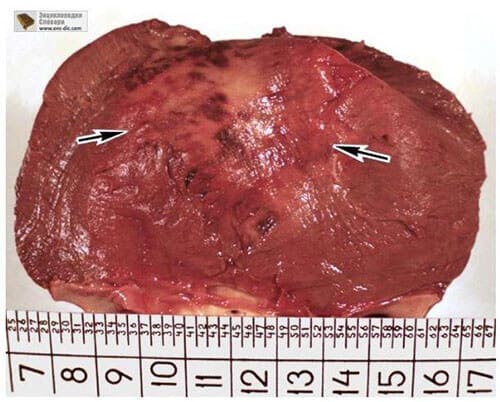

Prostatakrebs bei einem Mann mit 58 Jahren.